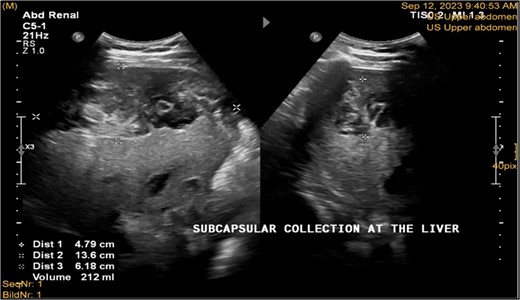

A 41-year-old male with a clear medical background, presented to the Emergency Department with right upper quadrant (RUQ) abdominal pain for two days, associated with fatty dyspepsia, anorexia, nausea, and vomiting. On arrival, his heart rate was 111 bpm with a blood pressure of 128/94 mmHg. On examination, a yellowish discoloration of skin and sclera was noted with a negative murphy sign. Investigations showed elevated liver enzymes (LFT). An initial abdominal ultrasound showed a distended gallbladder with a thickened wall and multiple stones, largest measuring approximately 1.4 cm, and a common bile duct measuring 5 mm (Fig. 1). A magnetic resonance cholangiopancreatography (MRCP) identified a tiny 4-mm mid-cystic duct stone without intrahepatic biliary dilatation. After the initial management, an emergency LC was performed, which posed minimal challenges. Fortunately, no intraoperative complications were reported. A drain was kept in the subhepatic area, and the patient was kept under close observation. Second day postoperatively, the patient experienced dizziness and an intense RUQ pain despite proper analgesia. His heart rate was 89 bpm with a blood pressure of 107/64 mmHg. Investigations showed a drop in hemoglobin level from 13.8 to 9.9 g/dl. An abdominal ultrasound showed a right subcapsular heterogeneous collection with a scalloped liver surface (Fig. 2). Therefore, an initial diagnosis of ISH post-LC was considered. Following the initial fluid resuscitation and blood transfusion, a further decline in hemoglobin level was noted reaching 8.8 g/dl. Further blood transfusion was commenced achieving stabilization. Further CT scan showed subcapsular hepatic hematoma measuring 7.1 × 19 × 21 cm, in its transverse, anteroposterior, and craniocaudal diameters, respectively, with no evidence of active extravasation (Fig. 3) confirming the final diagnosis of ISH post-LC. A multidisciplinary decision was made to continue conservative management after a proper explanation of the potential risk of sudden rupture of hematoma. The patient’s clinical condition and hemoglobin level, in addition to drain output, were meticulously monitored in the general ward, ensuring early detection of deterioration. Four days later, a follow-up CT scan revealed no new significant interval changes (Fig. 4). Nine days postoperatively, the patient was discharged with a follow-up appointment, which showed almost complete resolution.

Ultrasonography postlab chole, shows right liver lobe subcapsular heterogenous density collection with liver surface being scalloped and pushed away from the capsule. Volume was about 212 ml. Morison pouch and Lino renal pouch was free.